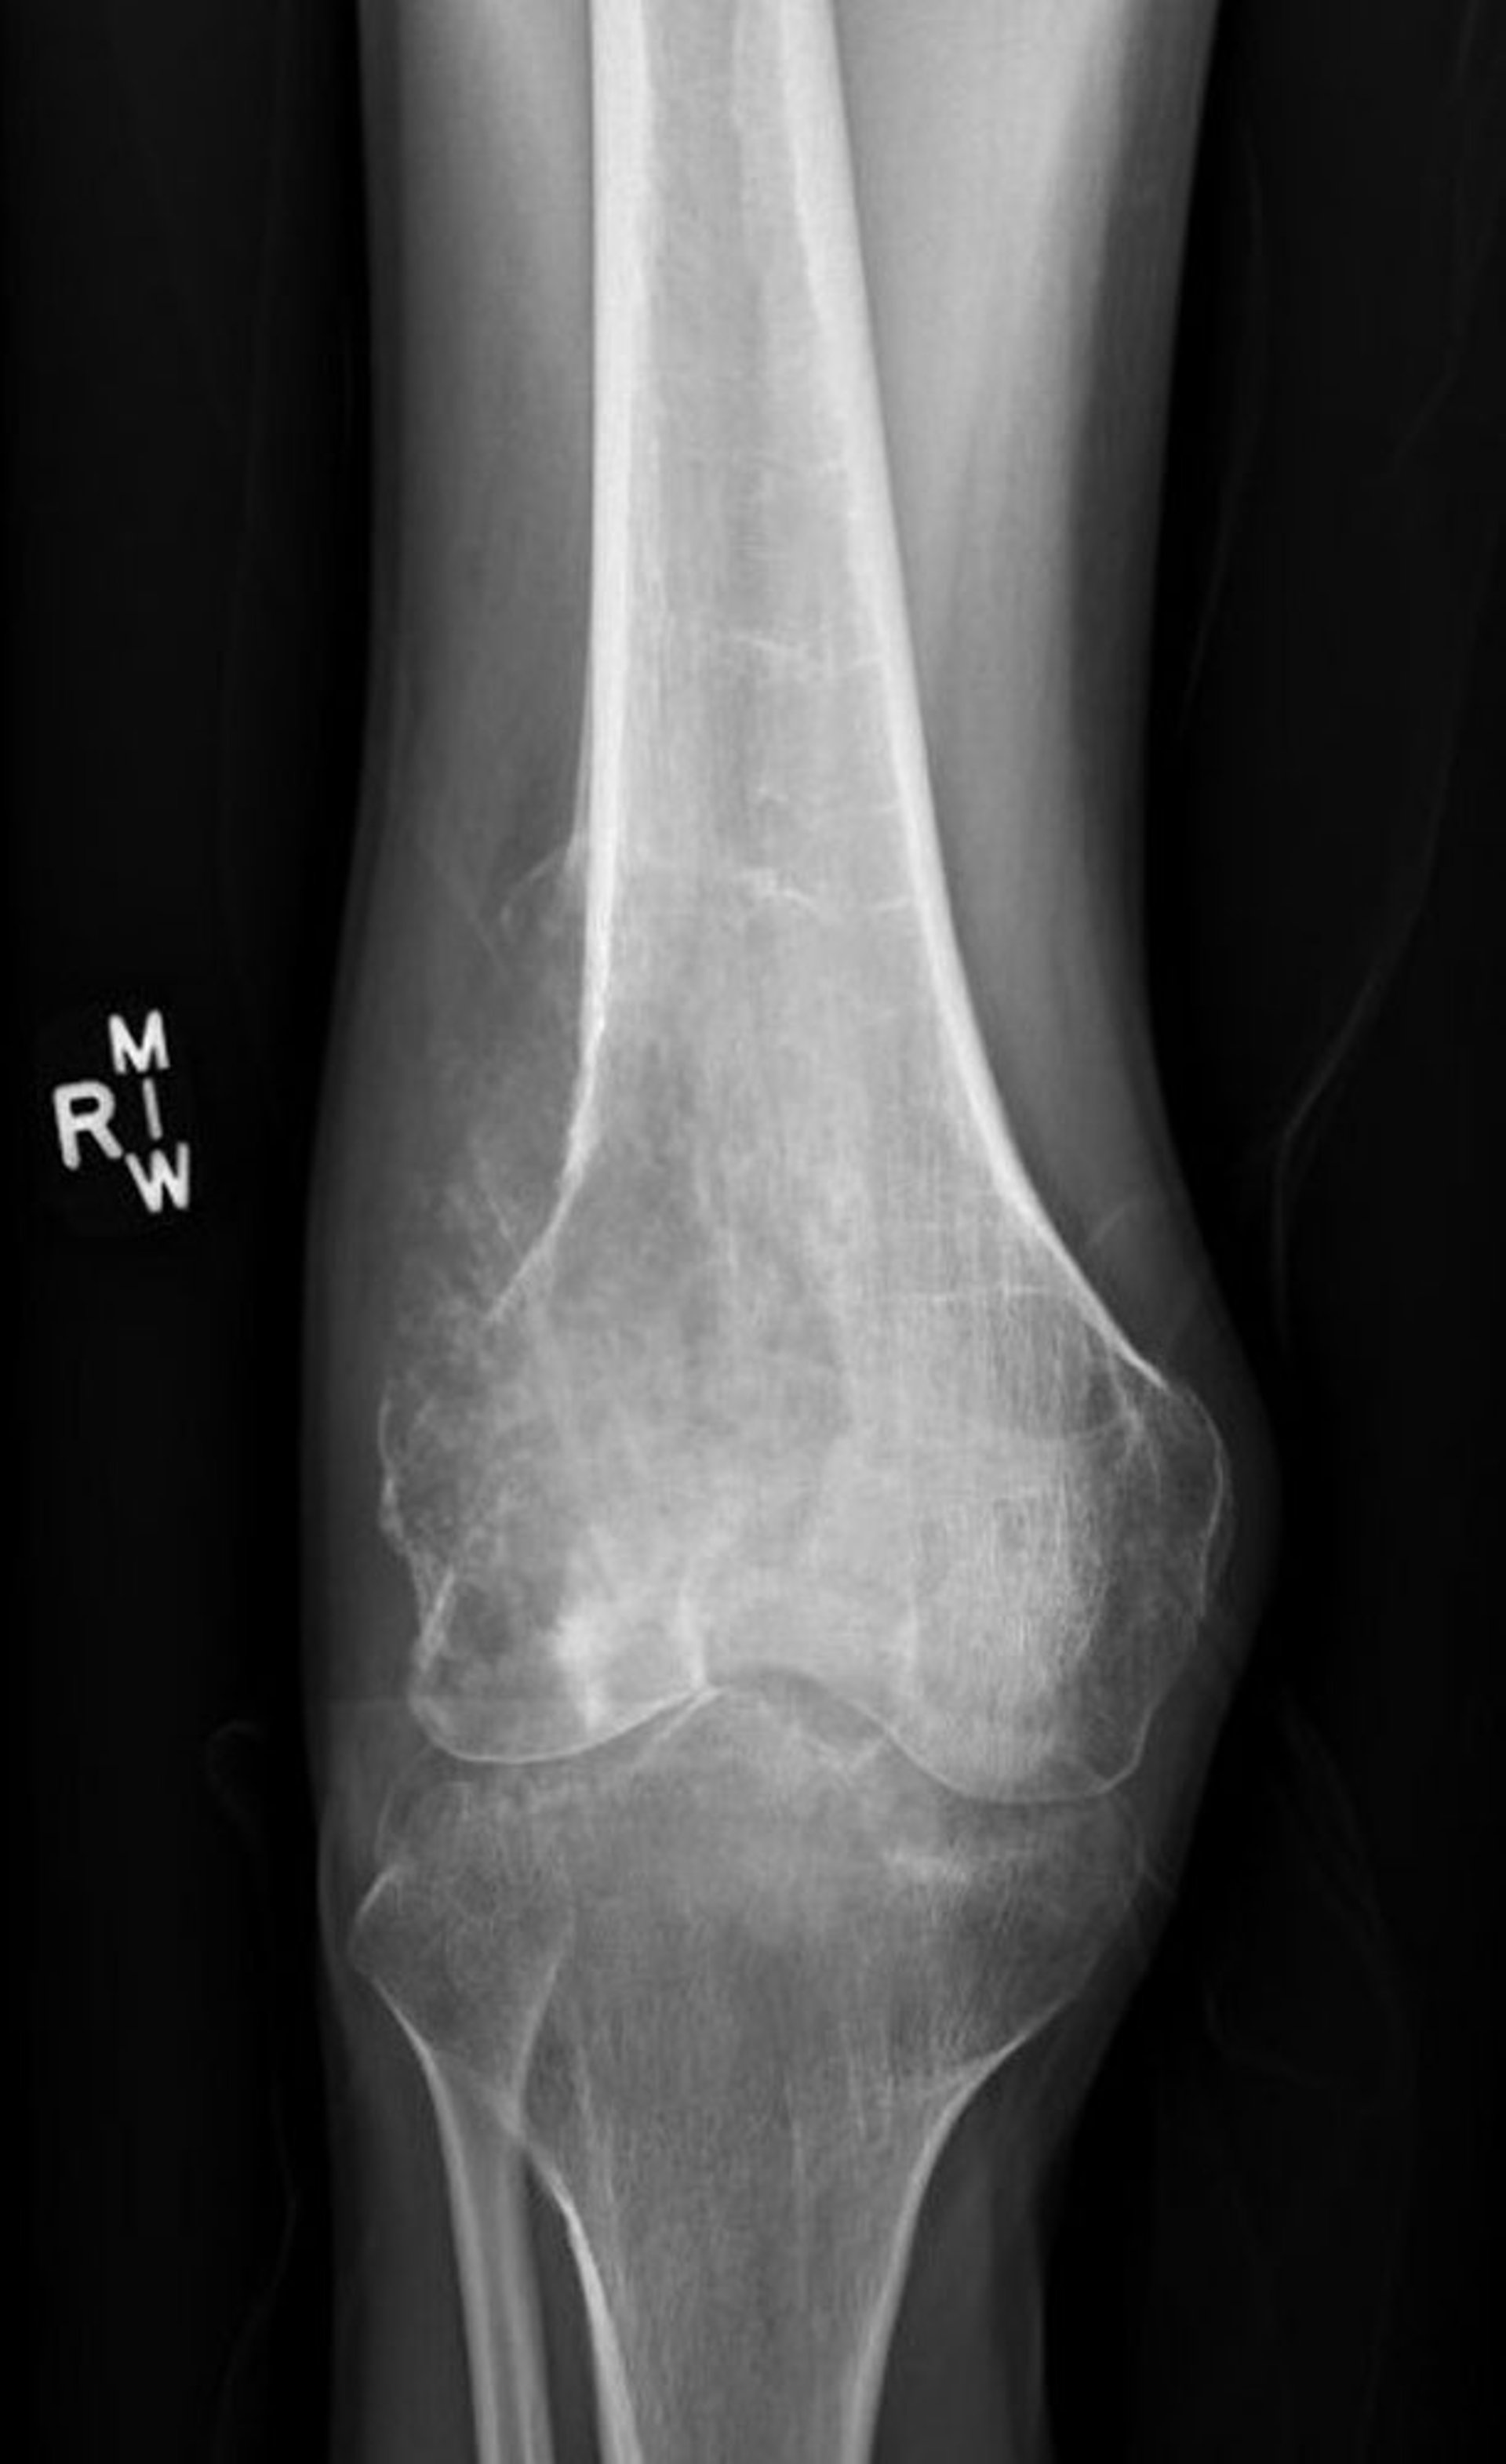

Esta radiografía de la rodilla muestra un osteosarcoma en el hueso del muslo (fémur), por encima de la rodilla.

Imagen cortesía de Lukas Nystrom, MD.